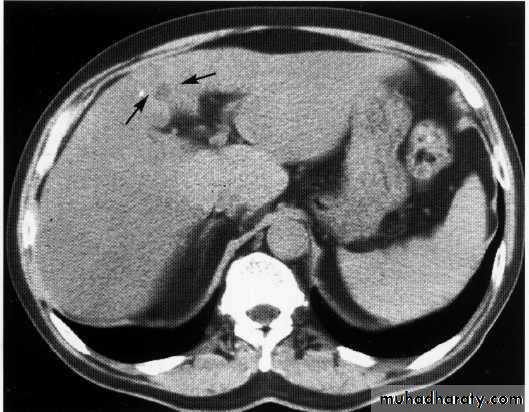

hydatid cyst